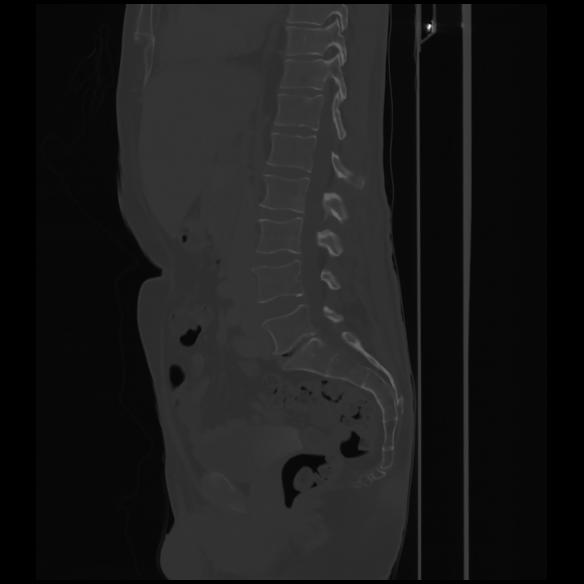

7 CUERPO,CE,Sagittal,3.000,CUERPO,Sagittal,